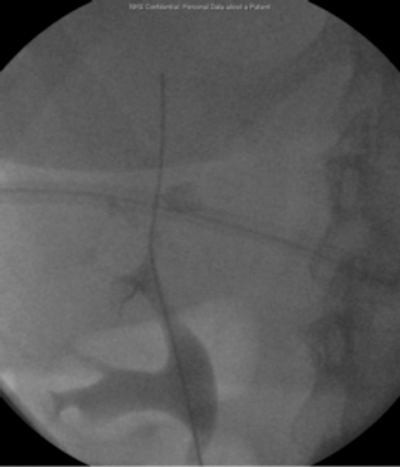

Pre-laparoscopy retrograde examination.